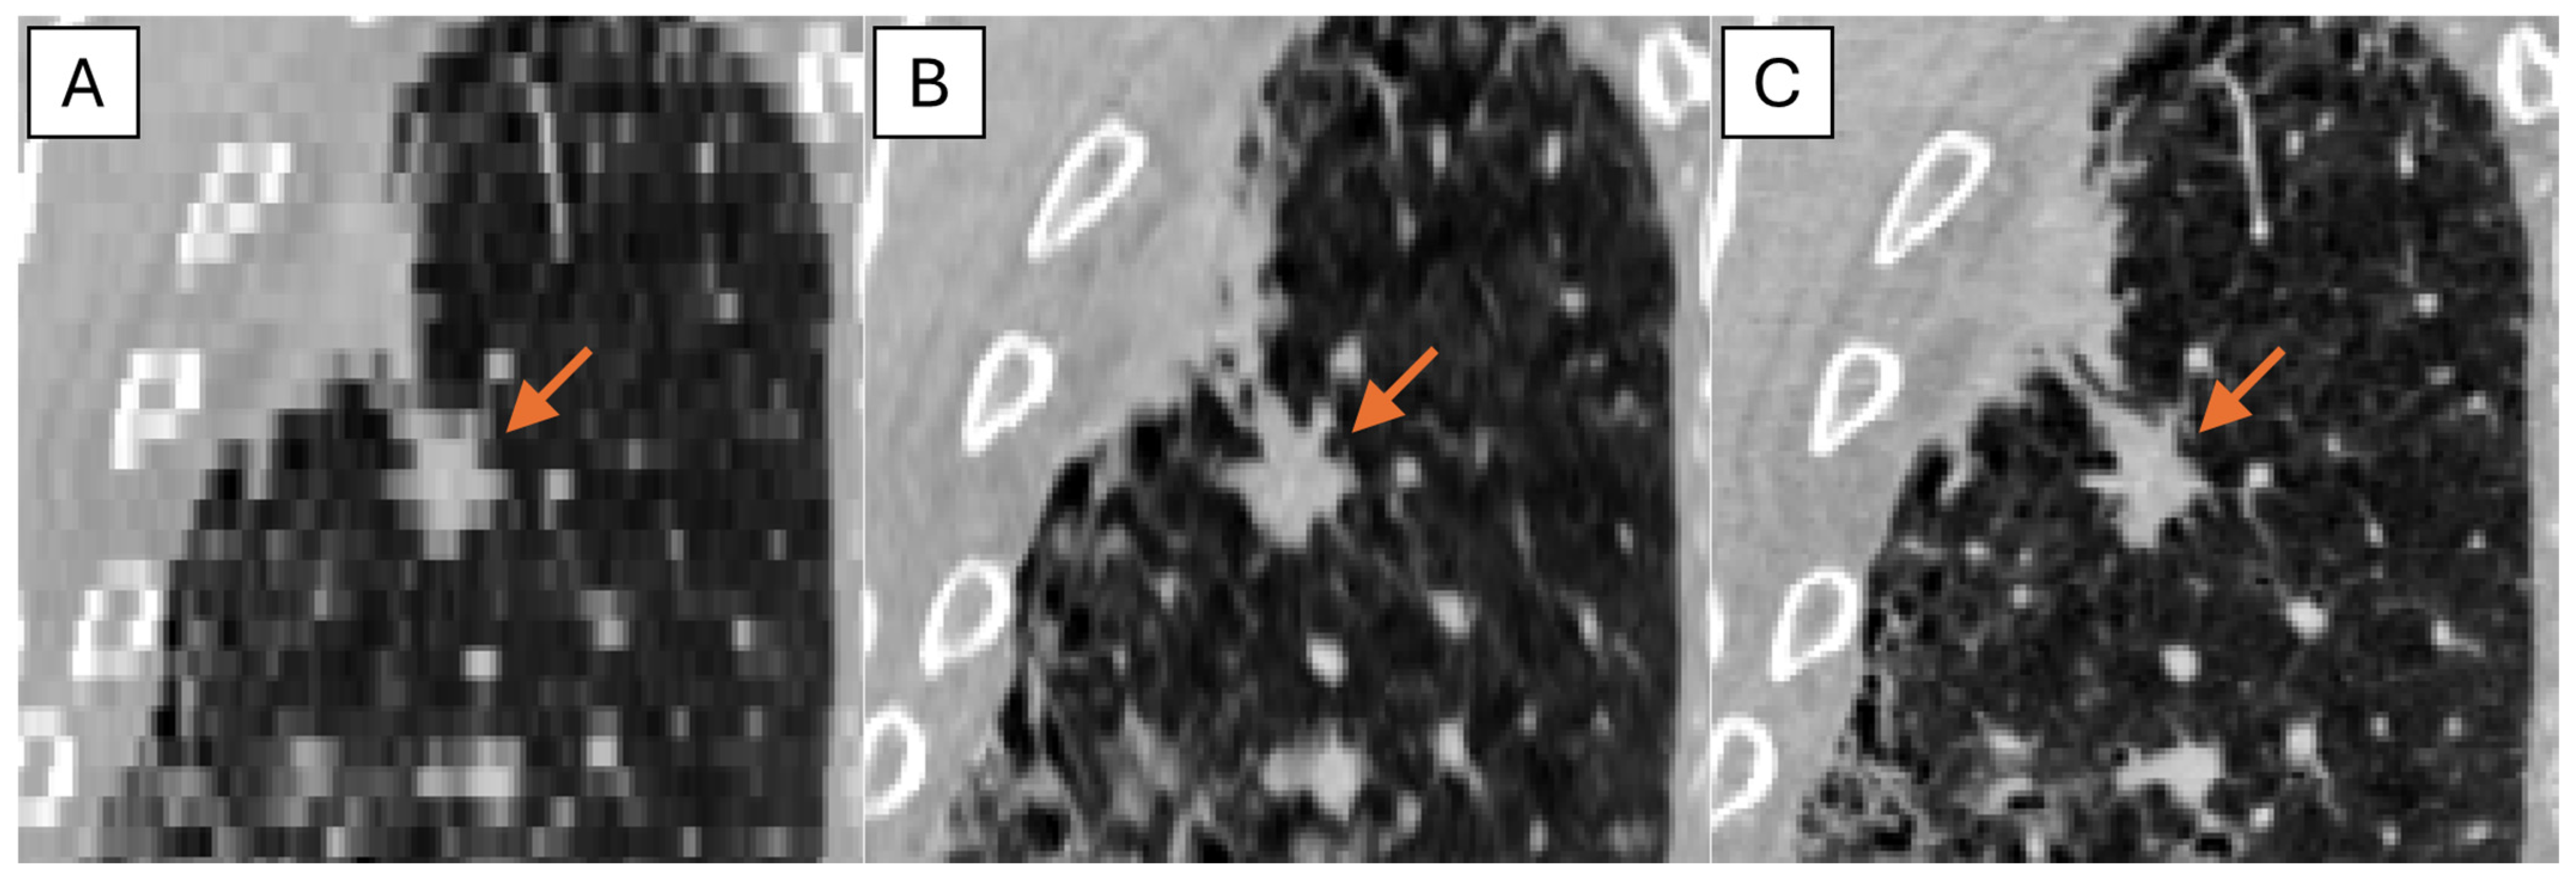

The representative thick-, generated-thin- and thin-slice coronal CT images of solid nodule and (ground glass nodule) GGN are shown in Figure 5 and Figure 6. The thick-slice CT images show staircase artifacts on both solid nodule and GGN, making accurate volume measurement and corresponding categorization nearly impossible, whereas generated-thin-slice CT images show image quality on par with thin-slice CT images, exhibiting clear nodule/GGN structures and well-defined pulmonary vessels delineations.

Figure 6. Coronal CT images of (A) thick-slice, (B) generated-thin-slice, and (C) thin-slice presenting GGNs as shown by the arrows.